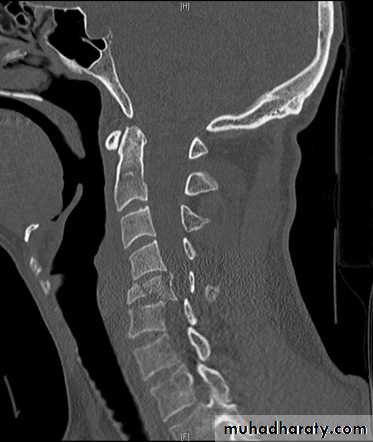

DIAGNOSISX RAY

frcature spine and peripheral nerve

Anterio posterior X ray radiograph.lateral radiographs with the head in flexion and extension may revealinstability that is not shown in the routine lateral film.

Computed tomography (CT)

and magnetic resonance imaging (MRI).